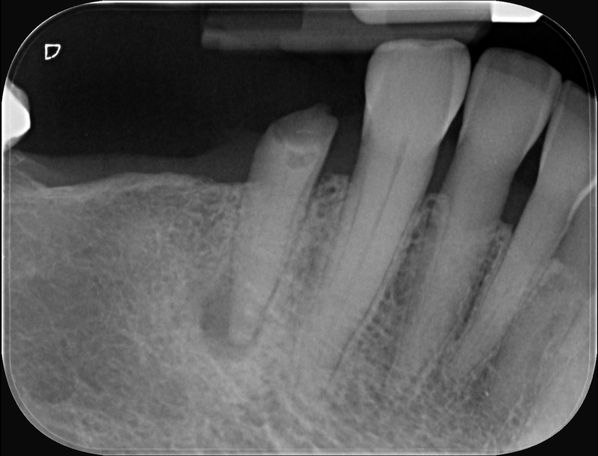

Who needs bone graft?

A person with bone loss in their jaw usually needs a dental bone graft. This procedure may be recommended if you:

- Are having a tooth extracted.

- Plan to replace a missing tooth with dental implant.

- Need to rebuild the jaw before getting dentures.

- Have areas of bone loss due to gum (periodontal) disease.

Socket preservation - Graft is placed in the socket immediately after a tooth extraction. It fills the void left behind by the missing tooth and prevents the sides of the socket from caving in.

Ridge augmentation - If your teeth have been missing for a while, the supporting jawbone may be thinner than it was before. Ridge augmentation increases the width and volume of the jawbone so it can provide a stable foundation for implants or other restorative options.